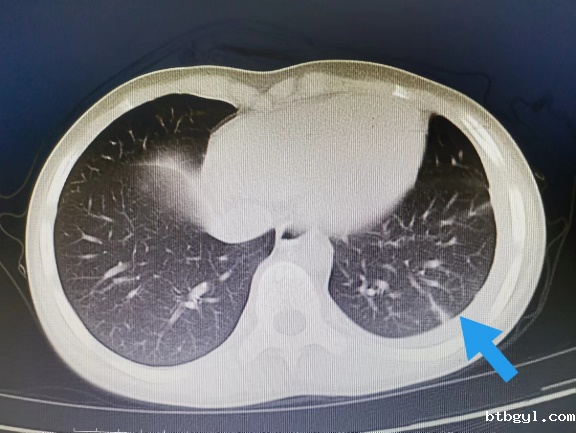

近日,一向身体健康的8岁的小男孩小阳(化名),几天前突然开始剧烈头痛,反复恶心、呕吐,奶奶赶紧把他送到我院就诊。 起初,大家认为小阳只是简单的感冒或则肠胃问题,普通检查没有找到病因,最终在颅脑CT提示下发现小阳“左侧枕叶脑出血伴血肿形成”。 患儿入院影像(左图为颅内出血、右图为胸腔积液及心包积液) 入住神经外科后,考虑到小阳近期并没有受过外伤,依据既往经验,小阳的脑出血可能是先天性血管畸形,但完善相关脑血管检查后却提示小孩脑血管正常,诊断一时陷入了僵局。 仔细问诊 查找蛛丝马迹 经过不断询问,副主任医师汪棋笙了解到小阳来自山区农村,且平时有喝生水和吃生螃蟹的习惯,汪棋笙似乎找到了诊断的关键。回顾了小阳血常规结果嗜酸性粒细胞较正常增高4倍,结合患儿心肺CT提示心包积液、胸腔积液,存在多器官损害表现,汪棋笙高度怀疑小阳就是肺吸虫感染、脑型肺吸虫病。 多方打探 从成都邀请工作人员上门检测 近年来肺吸虫病感染率非常低,肺吸虫血清抗体检测在周边各大医疗中心均已停止开展此项检查,诊断再次陷入困难。经多方打听,最终联系到可以开展此项检测的机构,为此,科室立即联系,邀请工作人员从成都赶来上门抽血检测。最终确立了肺吸虫感染、脑型肺吸虫病的诊断。 寻遍全省 获得特效药 尽管小阳的诊断已明确,可新的问题又再次出现,治疗肺吸虫的特效药物“吡喹酮片”医院及市场上已经无法购得。科室可谓是全员出动,寻遍各级医疗机构,最终从四川省疾控中心获得该药物,治愈了小阳。 患儿出院影像(颅内出血、胸腔积液及心包积液已基本吸收) 特别提醒: 饮用生水或吃了未经煮熟的青蛙、蛇等肉类,容易导致寄生虫感染,寄生虫可进入血管,并通过血液循环进入大脑内生存,引发相关脑病。 肺吸虫是什么? 肺吸虫又称并殖吸虫,是甲壳类哺乳动物的常见人兽共患寄生虫。当它们在组织中迁移时会引发嗜酸性反应,因此我们可以在化验单上看到嗜酸性粒细胞增多。肺吸虫感染人体后主要寄生于肺部,还可异位至脑部、腹部及皮下等部位,引起相应的器官组织病变。 哪些习惯容易招虫? 近年来发病率有所下降,但在部分人或因饮生水、生食或者半生食虾蟹的习惯,导致该病时有发生。 如何预防肺吸虫感染? 1.不要随意喝生水,尤其是河水、小溪水等。 2.切勿吃生的淡水螃蟹、小龙虾等,一定要煮熟。 3.避免食用未煮熟的其它淡水甲壳类动物或来自污染水源的淡水鱼类。 神经外科联系电话:0830-5216264